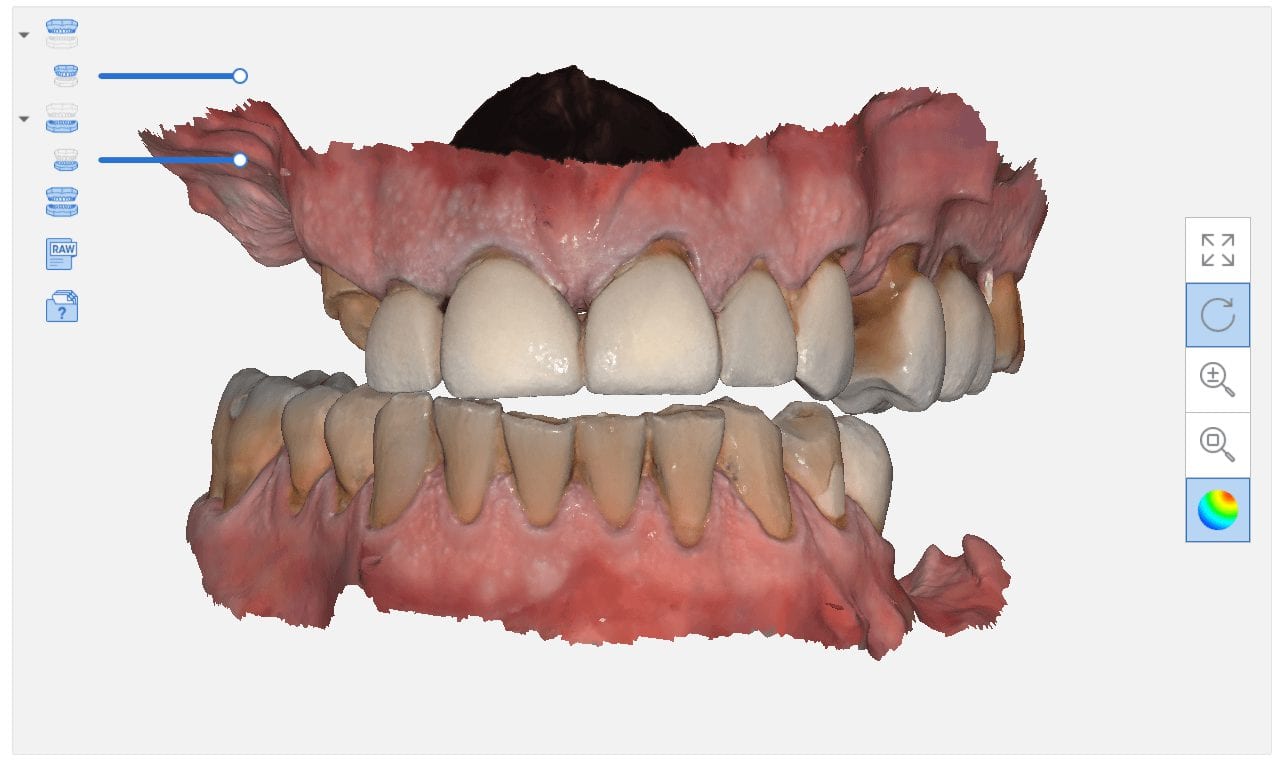

April 5, 2020If you’re experienced with CAD/CAM technologies in dentistry, you probably already know how important file types and system integrations can be for the outcome of a project. In this video, […]